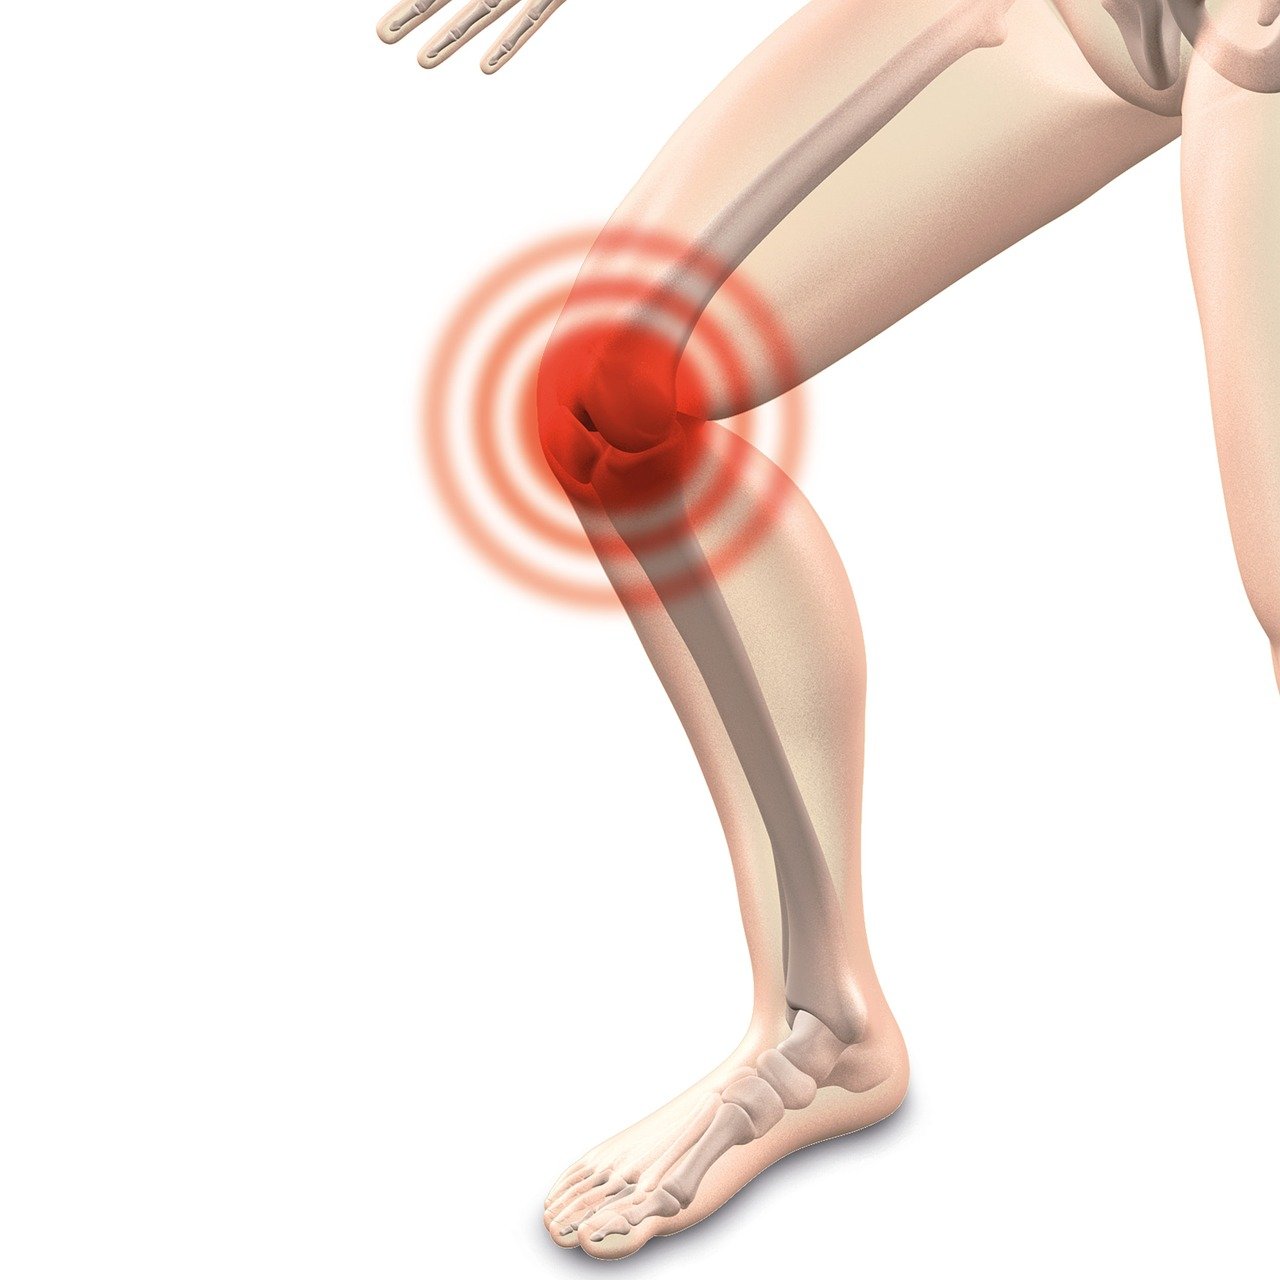

무릎통증 원인 증상 총정리 서론

이번 포스트에서는무릎통증 원인 증상 총정리 하여 자히 알아보고, 이를 예방하고 관리하는 방법을 소개하고자 합니다. 아시다시피 무릎통증은 다양한 원인으로 발생할 수 있으며, 일상 생활에 큰 불편을 초래할 수 있습니다. 저도 무릎통증때문에 꽤나 고생한 적이 있었는데요. 무릎통증에 대한 올바른 이해는 효과적인 치료와 예방의 첫걸음이라고 생각합니다. 우리 같이 무릎통증 원인 과 증상에 대해 자세히 알아보도록 하시죠.

무릎통증 원인